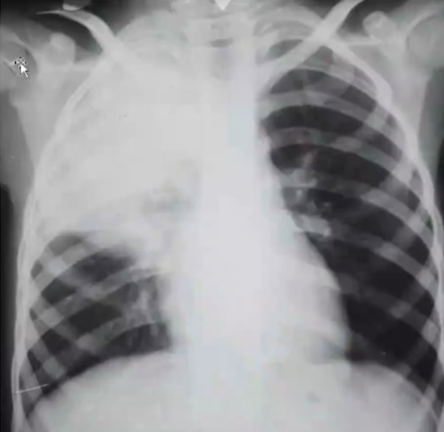

Rx toracică, incidență P-A

DESCRIERE: DAS + stază

indice cardiotoracic ↑

semne de dilatare a AS:

dublu contur inferior drept (contur dublu “festonat“)

deschiderea unghiului de bifurcație a traheei >120 grade

bombarea arcului mijl stg (golful pulm) → HTP

semne de stază pulm: dilatarea hilurilor + apicalizarea circulației + linii Kerley B

DX: stenoză mitrală

DD: insuf mitrală, boală mitrală, stenoză Ao